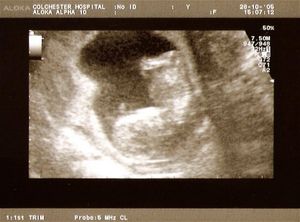

산부인과 초음파는 태아의 크기로 임신 주수를 측정하고, 태아의 수와 태반을 확인하며, 자궁외 임신과 임신 초기 출혈을 평가하는 데 일상적으로 사용된다. 태아의 성장이 다른 요인에 의해 크게 영향을 받기 전인 임신 초기, 특히 첫 번째 삼분기에 가장 정확하게 측정된다.[22] 초음파는 또한 선천적 기형(또는 기타 태아 기형)을 감지하고 생물리학적 프로파일 (BPP)을 결정하는 데 사용되며, 태아 구조가 더 크고 발달된 임신 두 번째 삼분기에 일반적으로 더 쉽게 감지할 수 있다.[23]

X-선 및 전산화 단층 촬영 (CT)은 특히 임신 초기에는 이온화 방사선으로 인해 사용되지 않으며, 이는 태아에게 기형 발생 효과가 있다.[24] 자기 공명 영상 (MRI)이 태아에게 미치는 영향은 입증되지 않았지만,[25] 이 기술은 일상적인 관찰에는 너무 비싸다. 대신, 산부인과 초음파는 방사선을 방출하지 않고 휴대 가능하며 실시간 영상을 허용하므로 임신 초기 및 임신 기간 동안 선택되는 영상 방법이다.[26]

잦은 초음파 검사의 안전성은 확인되지 않았다. 그럼에도 불구하고, 성별 스캔, 3D 및 4D 스캔과 같이 의료적 목적 없이 추가 스캔을 선택하는 여성의 수가 증가하고 있다.[27] 정상적인 임신에서는 임신 낭, 난황 낭, 태아 극이 나타난다.[28]

임신 주수는 6주차 이전에는 평균 임신 낭 직경(MGD)을 평가하고, 6주차 이후에는 머리-엉덩이 길이(crown-rump length)를 평가하여 측정할 수 있다. 다태 임신은 존재하는 태반과 양막의 수로 평가된다.[29]